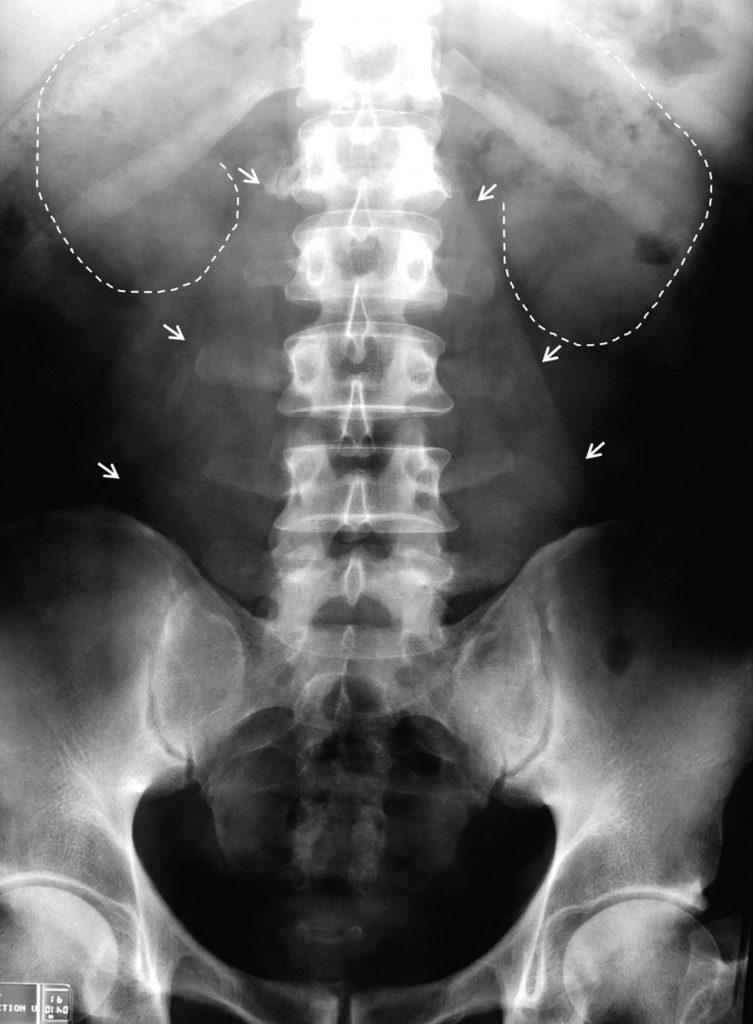

Fig. 19.4. Cliché d’abdomen sans préparation centré sur l’appareil urinaire réalisé vessie vide.

Ombres rénales (lignes pointillées). Bords des muscles psoas (flèches).

Source : CERF, CNEBMN, 2022.